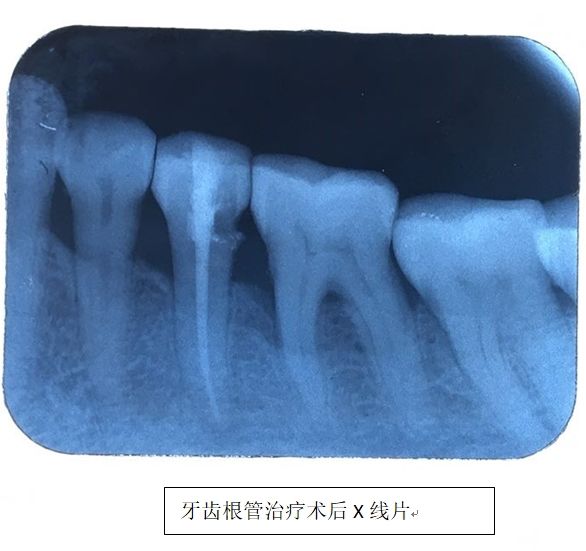

听闻街坊邻居说起,湖南航天医院的口腔科就诊环境有了极大改善,医疗设施越来越完备,医疗技术越来越高,娭毑遂来院就诊。为她进行诊疗的是邓旋医师,在详细询问病史和缜密地检查后,邓旋判断娭毑的症状是由牙齿引起,初步诊断为牙髓炎,排除张娭毑自己怀疑的神经疾患。找出病因后,邓旋医师便开始着手对张娭毑的患牙进行治疗。

过了几天,张娭毑欣喜不已地来院复诊。原来患牙经过根管治疗后,左面部神经疼痛症状明显消退,眼泪也不异常流出了,脸上露出了微笑,心情也开朗了许多,生活质量也有了极大提高。医生随诊时还听说最近她还和家人出去旅游了……

牙髓炎是发生于牙髓组织的炎性病变,当牙体硬组织因各种原因遭受破坏时细菌就可侵入并感染牙髓。可发生于任何有牙齿的年龄阶段。它有自发性阵发性疼痛的特点,有夜间痛,从而影响睡眠。温度刺激会引发或加剧疼痛,而在牙髓炎晚期,还表现为“热痛冷缓解”的特点,这时患者常常通过含冷水来暂时止痛。疼痛发作时,患者大多不能明确指出患牙所在,且疼痛常常沿着三叉神经第二支或第三支分布区域放射至患牙同侧的上、下颌牙齿或头部、颞部、面部、耳部等部位。